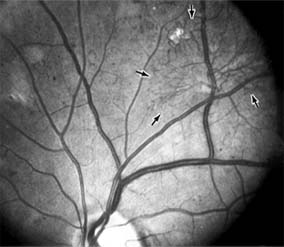

Figure 10-24

Figure 10-24: A frond of neovascular tissue (arrows) is seen along the superotemporal vascular arcade in this eye with proliferative diabetic retinopathy.